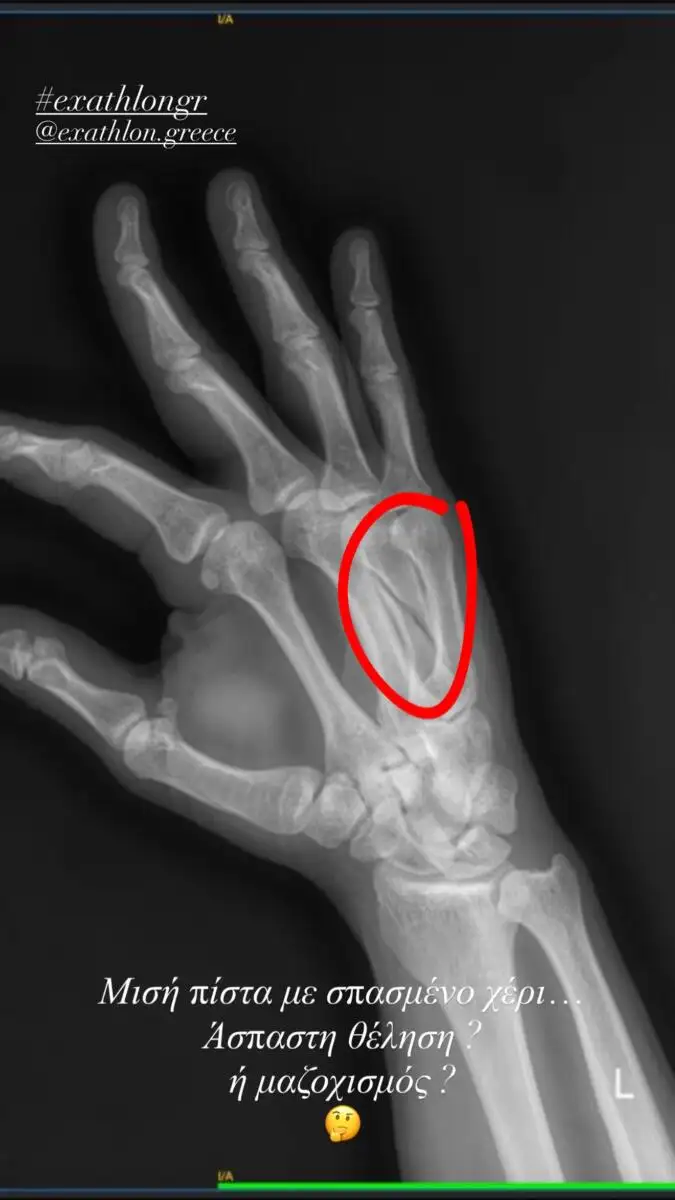

Το περιστατικό σημειώθηκε στον τελευταίο αγώνισμα, όπου ο παίκτης τραυματίστηκε σοβαρά στο χέρι του. Οι γιατροί διέγνωσαν σπάσιμο, κάτι που σήμανε και το υποχρεωτικό τέλος της πορείας του στο παιχνίδι.

Λίγες ώρες μετά την προβολή του επεισοδίου, ο Στάθης έκανε την πρώτη του ανάρτηση, ανεβάζοντας φωτογραφία με την επίσης τραυματισμένη Εύη Σαλταφερίδου, δείχνοντας το χέρι του στο γύψο αλλά και ένα χαμόγελο που αποδεικνύει ότι παραμένει δυνατός.